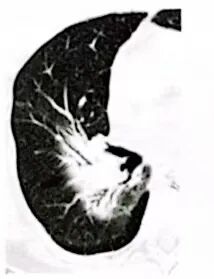

3. 放射性肺炎

表现:干咳、发热、气促,是胸部放疗需要重点关注的急性反应。

(毛玻璃样改变)

(斑片状改变)

表现:这是放射性肺炎的远期结果,部分受损的肺组织被没有弹性的“瘢痕”组织所替代。患者可能感到活动后气促、慢性干咳。CT上常显示照射区域有固定的条索状阴影。